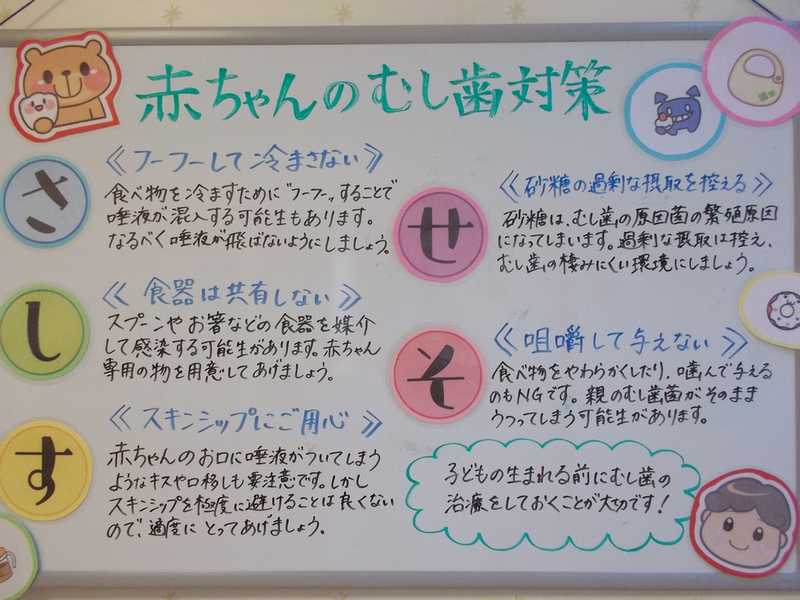

新テーマは赤ちゃんの虫歯予防対策。簡潔に「さしすせそ」で表現してあります。

一昔前に比べて子供の虫歯は、歯に関する情報が入手しやすくなったことや、様々なオーラルケアグッズが開発・販売されるようになり、減少傾向にあると言われています。しかし虫歯は感染症なので、一度うつるとどんなに頑張ってハミガキしても次々と出来てしまう場合があり、そもそも感染させない水際対策が肝心です。第一子は気を付けていたけど、二番目、三番目となると気が緩み、兄弟の影響もあって虫歯だらけ…。そんなケースは多々あります。いかにうつさないか。そのための5箇条、ママパパだけでなく、お祖父ちゃんお祖母ちゃんも家族みんなで実践してみてくださいね^^